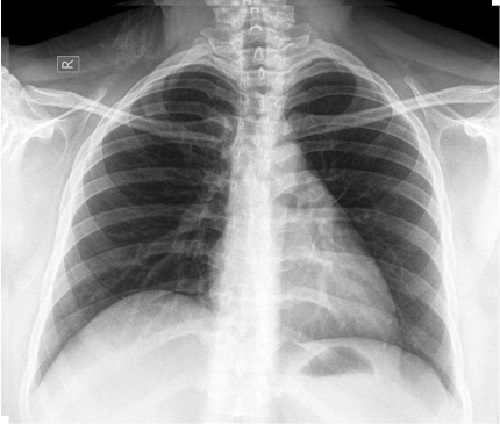

Siendo la principal causa de muerte por cáncer en el mundo, el cáncer de pulmón cada año cobra la vida de 1.8 millones de personas y se presentan 2.5 millones de nuevos casos de acuerdo con GLOBOCAN 2022. El cáncer de pulmón de células no pequeñas es el tipo predominante, representando aproximadamente el 85% de los casos, y de estos hasta un 4% se deben a mutaciones del gen HER2, asociadas con un mal pronóstico y una mayor incidencia de metástasis cerebrales.

Las mutaciones del gen HER2 pueden provocar una producción celular descontrolada, inhibición de la muerte celular y, en consecuencia, crecimiento y propagación tumoral. Es aquí donde zongertinib actúa como un inhibidor de la tirosina quinasa del gen HER2, bloqueando la proteína que permite que las células cancerosas se multipliquen sin control. 3,5